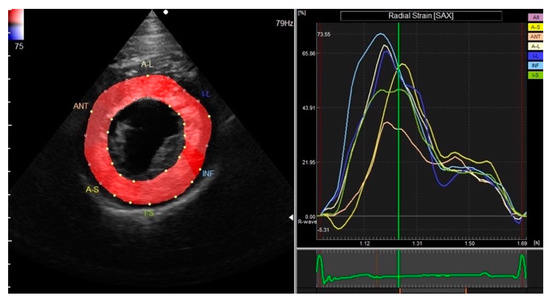

3.2. Two-Dimensional Speckle-Tracking Echocardiography

| GRS | 39.46 ± 12.46 | 37.93 | 34.63–44.29 | 19.46–66.46 |

| GCS | −12.99 ± 2.46 | −12.92 | −13.94–−12.04 | −19.40–−9.32 |

| STI | 65.74 ± 24.78 | 62.20 | 56.13–75.35 | 24.58–119.00 |